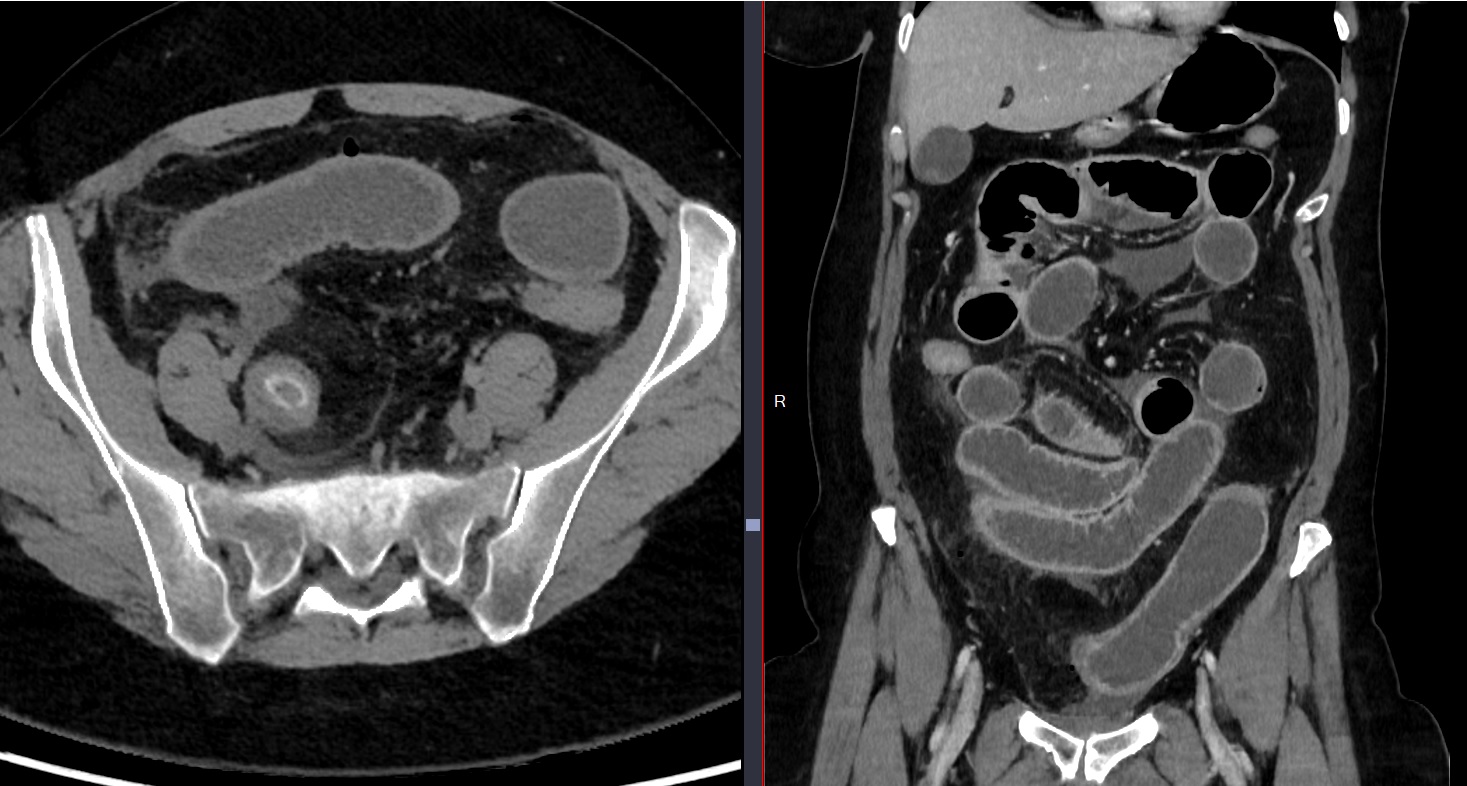

Closed loop

Clsoed Liip sur brides